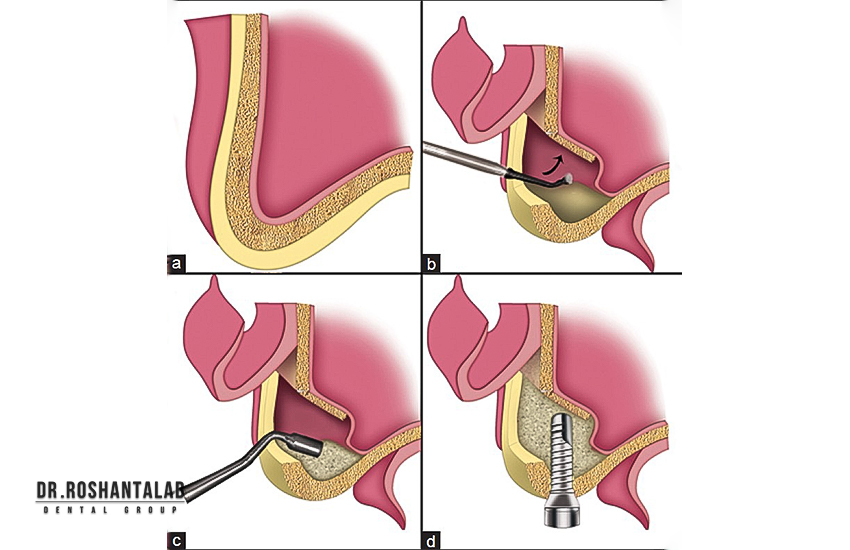

اگر استخوان فک کافی نباشد، جراحیهایی مانند سینوس لیفت یا پیوند استخوان لازم است که قیمت را افزایش میدهد. استخراج دندان، درمان عفونت لثه یا استفاده از بیهوشی نیز هزینههای جانبی اضافه میکنند.